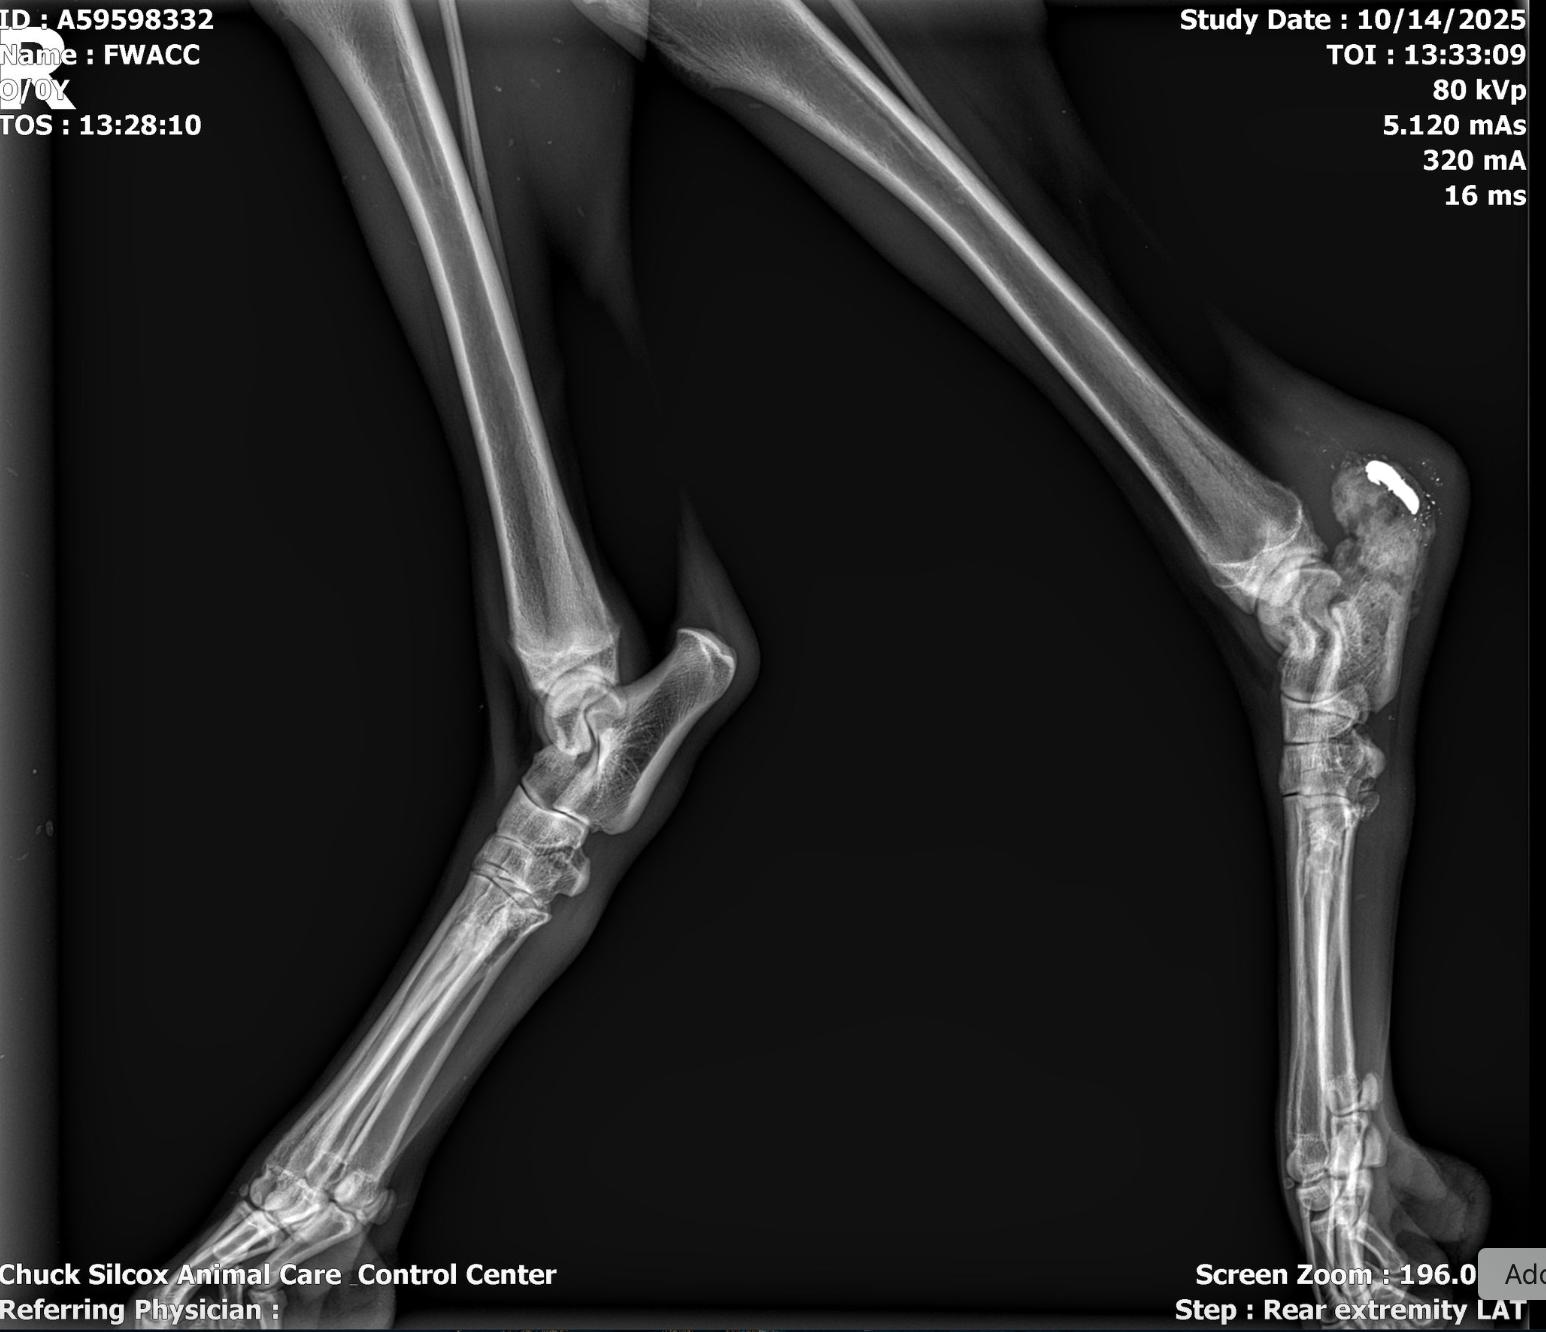

When Raven was found, he was extremely skinny and non weight bearing on his left rear leg. He developed an upper respiratory infection which developed into walking pneumonia, which has been successfully treated. X-rays of his rear leg showed a small piece of metal lodged in his hock. Because he is now using his leg normally and is no longer bothered by it, the vet determined leaving it alone was the best option,